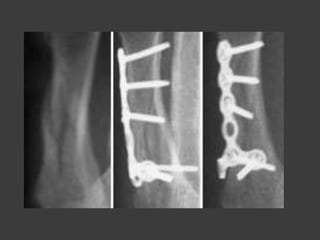

Fx diafisarias de los

metacarpianos

Transversales

Oblicuas

conminuta

Metodos de reducción

Transversales

Oblicua

Conminuta